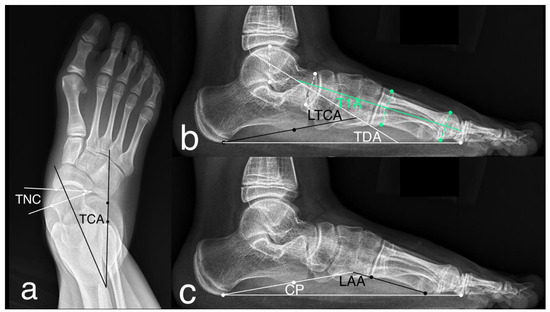

| Radiographic Assessments | AP | Talonavicular coverage | 38 (25–48) | 15 (5–25) * |

| Talocalcaneal angle | 35 (18–50) | 27 (19–32) * | ||

| Lateral | Talar-first metatarsal angle | 29 (16–39) | 10 (1–22) * | |

| Talar declination angle | 42 (26–53) | 28 (21–34) * | ||

| Lateral Talocalcaneal angle | 52 (33–62) | 39 (28–48) * | ||

| Longitudinal arch angle | 168 (166–173) | 166 (161–172) * | ||

| Calcaneal pitch | 10 (8–15) | 12 (7–16) * | ||